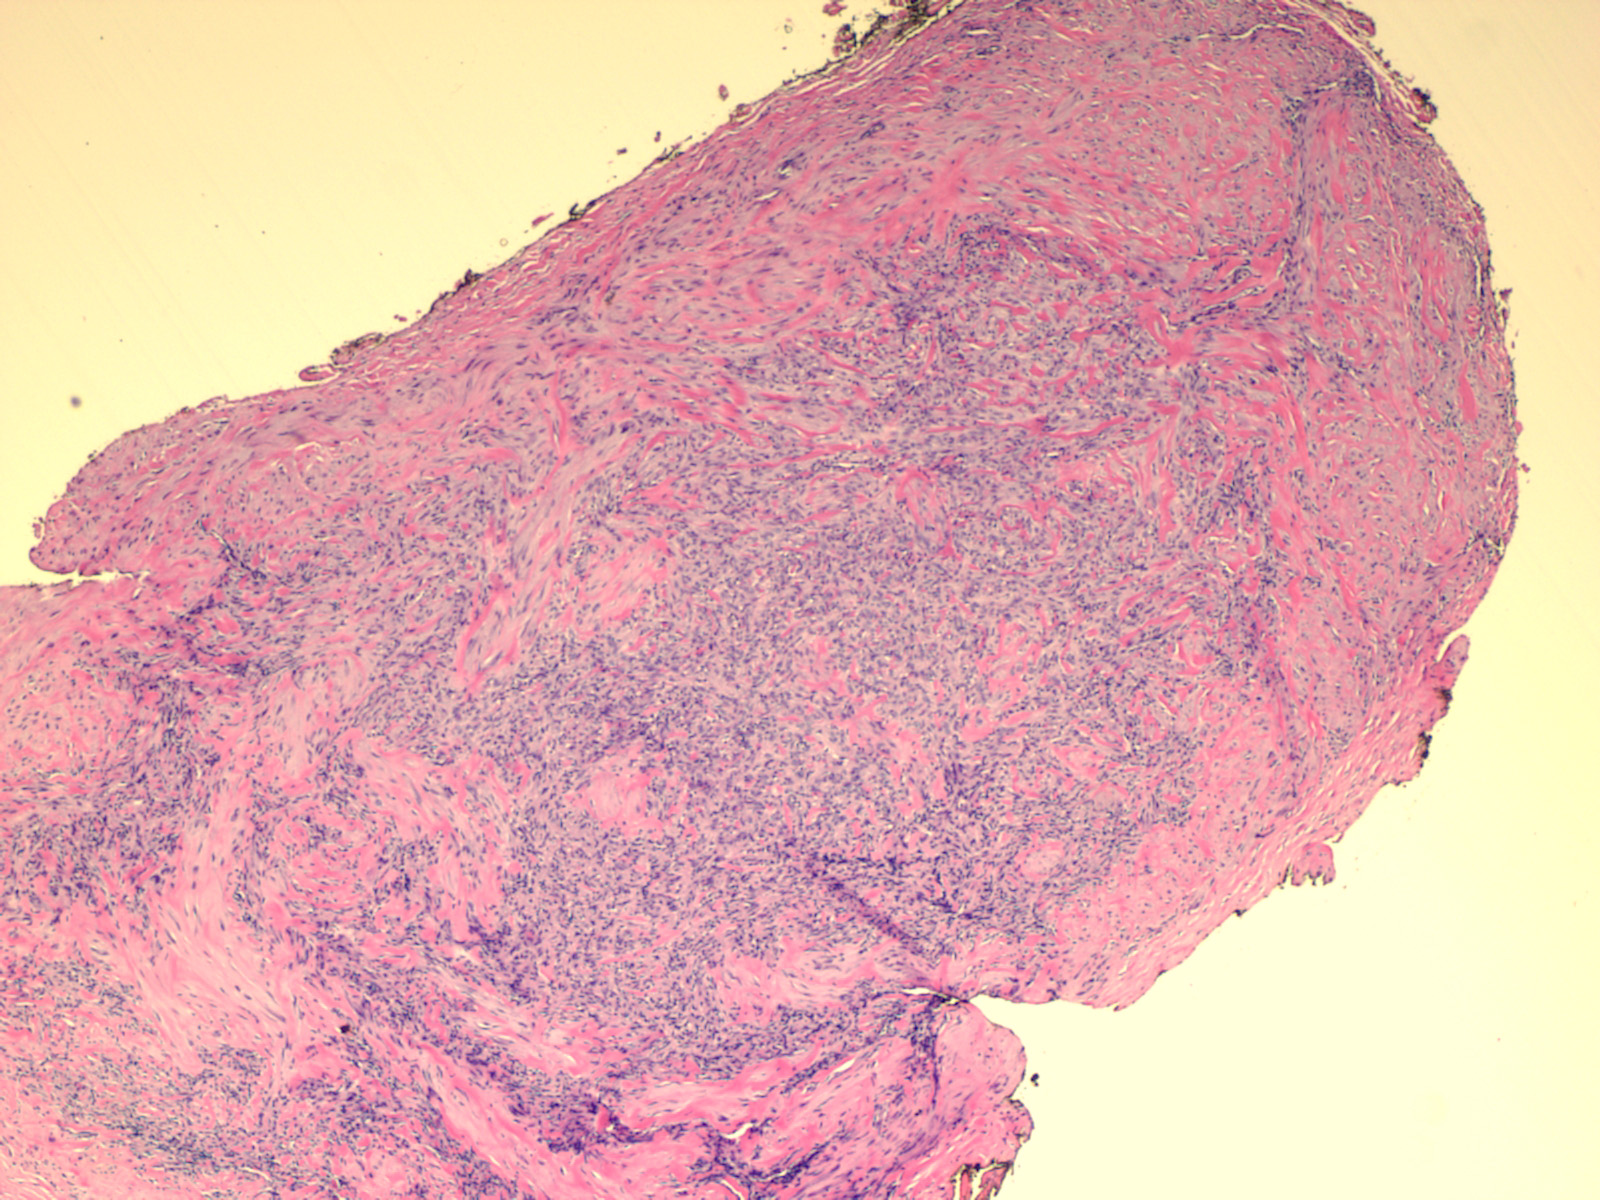

Myofibroma = الورم الليفي العضلي